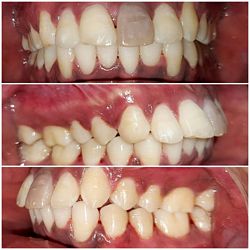

Intra-oral : Pre & Post treatment : Frontal View : 10 mm Overjet Reduced

Intra-oral : Pre & Post-treatment : Frontal View